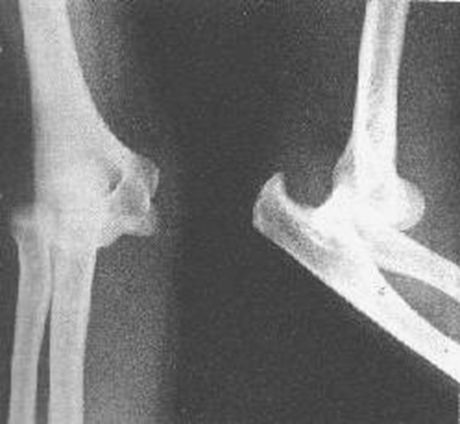

肘关节脱位

肱骨髁上骨折